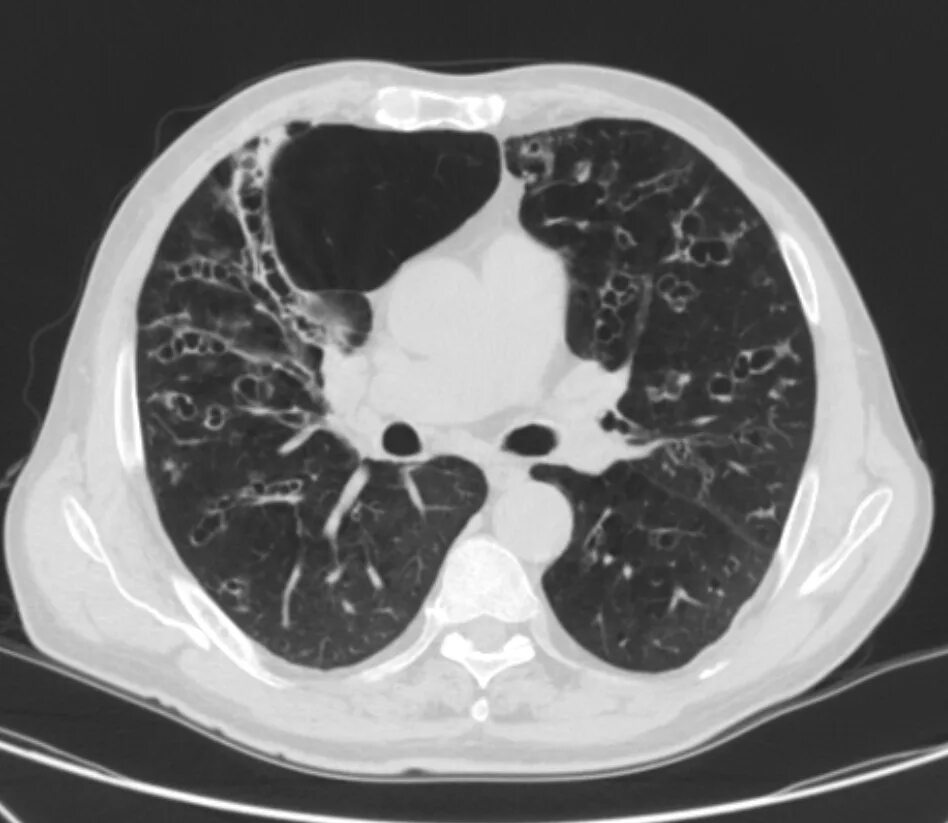

Заболевание кт